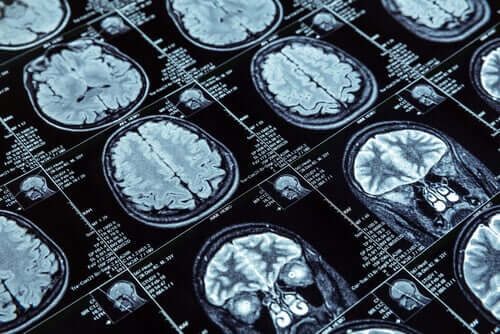

Aby przeprowadzić badania, wykonali magnetyczny rezonans jądrowy na ponad 600 osobach, które w momencie badania obrazowego miały 45 lat. Te 600 osób jest częścią większej grupy badawczej składającej się z ponad 1000 osób. Nowozelandczycy badają ich przypadki już od dzieciństwa.

Zmierzyli grubość kory mózgowej i ilość istoty szarej poprzez rezonanse, które wykonali na uczestnikach badań. Dane te pozwoliły na porównanie tych, którzy przejawiali zachowania antyspołeczne i tych, którzy tego nie robili.

W pierwszej grupie badacze zauważyli ważne rzeczy. MRI mózgu tych osób wykazało kurczenie się kory mózgowej w porównaniu z innymi. Ponadto miały nieco mniejszą ilość istoty szarej.

To, co jest oczywiste, to zmiana w architekturze mózgu, którą może mieć niewielka część populacji. I może mieć ona związek z antyspołecznymi typami zachowań. Te zmiany mogą tłumaczyć antyspołeczną osobowość, która uporczywie manifestuje się przez lata.

Na przykład nastolatki z problemami antyspołecznymi miały zmiany w obszarach czołowych i skroniowych mózgu. Co więcej, skazańcy stosujący przemoc mają mniej szarej materii.

W szczególności naukowcy badali strefę emocji w mózgu, aby znaleźć związek. Zakładając, że problemy aspołeczne wynikają z braku empatii, logiczne było szukanie zmian w tym obszarze. Wyniki wskazują, że aspołeczni nastolatkowe mają mniejsze ciało migdałowate w mózgu, a właśnie to miejsce jest siedliskiem empatii.